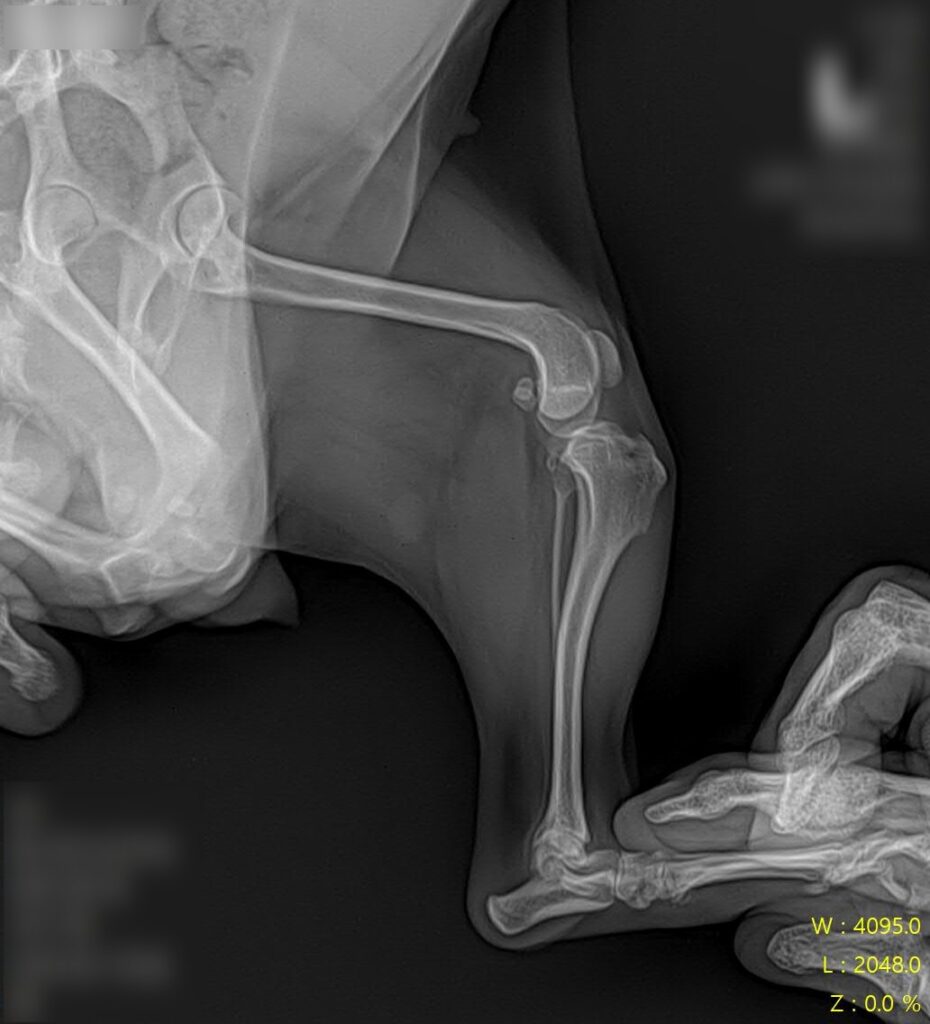

마취 전 방사선 검사 / 출처: 라온동물메디컬센터

정형학적 검사와 방사선 영상 검사를 진행한 결과, 슬개골탈구 4기(말기, terminal) 소견이 확인되었습니다. 슬개골이 완전히 고정 탈구된 상태였고, 활차구의 심각한 평탄화와 경골 조면의 내측 편위, 다리뼈의 비틀림이 동반되어 있었습니다.

2년 전 3기 진단 당시와 비교하면 그 사이 조용히, 그러나 빠르게 진행된 것이었어요. 보행이 크게 불편해 보이지 않았던 이유는 강아지가 변형된 뼈 구조에 스스로 적응하며 걷고 있었기 때문입니다.